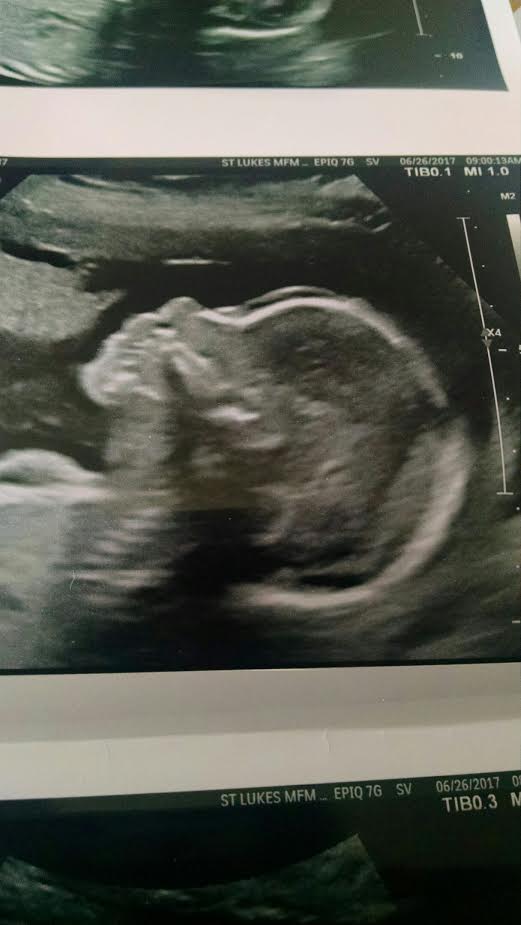

So I would like to see that everyone thinks of these pics from the skull theory. I was 20w exactly.